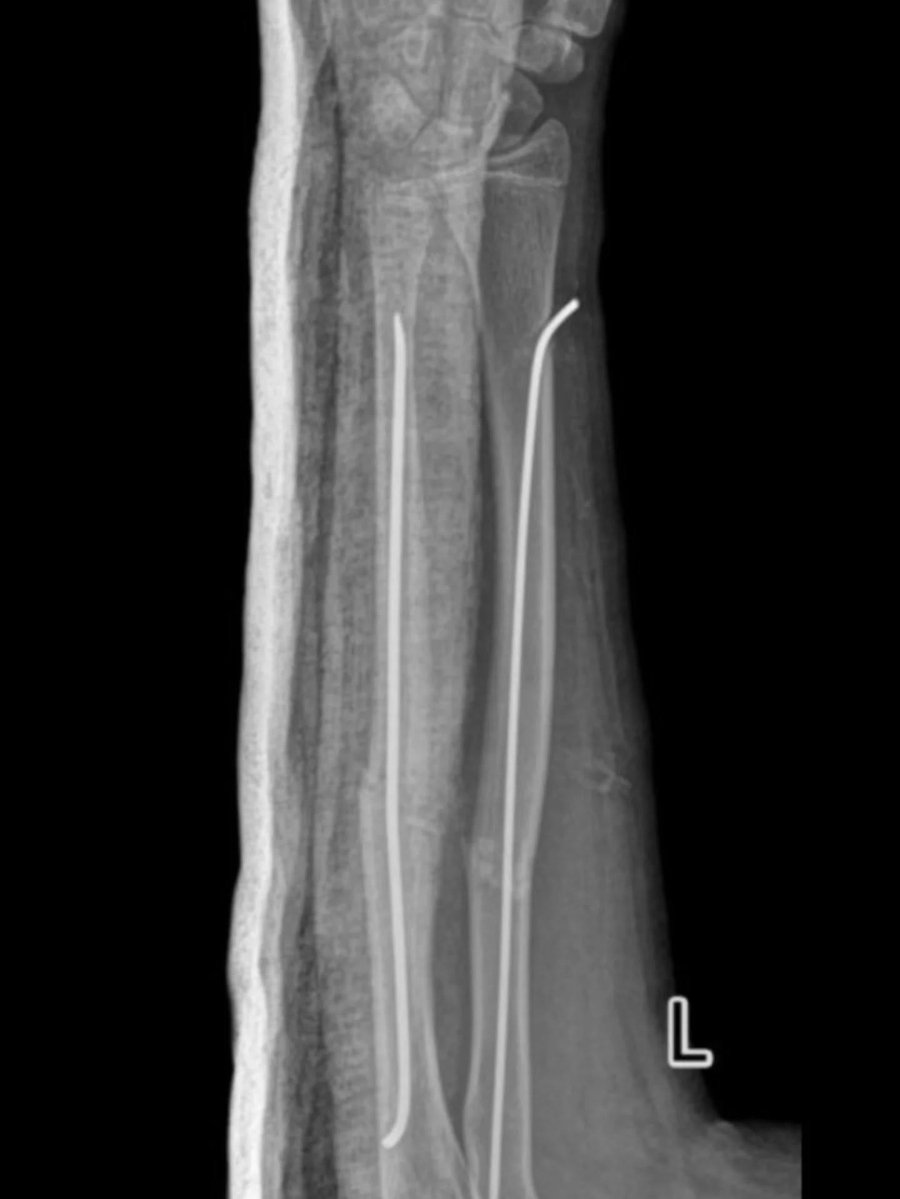

Ортопеди-травматологи Володимирського ТМО провели малоінвазивну операцію 14-річній дівчинці. Їй виконали закриту репозицію кісток лівого передпліччя з внутрішньокістковою фіксацією з ТЕНами.

Юній пацієнтці через два невеликі проколи шкіри передпліччя вправили зміщені уламки кістки без хірургічного розрізу, за допомогою спеціальних інструментів, відновлюючи правильне анатомічне положення кістки. Втручання проводилося під рентген-контролем.